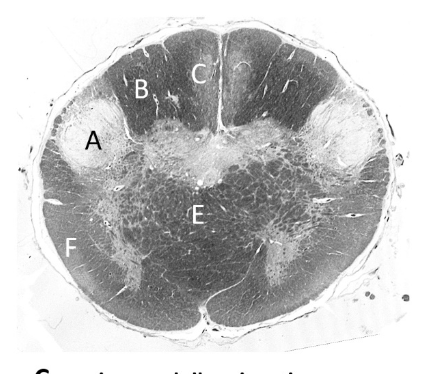

at what level is this?

mid pons

what is a?

cerebellum

what is b?

superior cerebellar peduncle

what is c?

middle cerebellar peduncle

what is d?

trigeminal nerve

what is e?

pyramidal fibres

what is f?

transverse pontine fibres

what is g?

4th ventricle

what is h?

median longitudinal fasciculus (p)

what is j?

medial lemniscus (p)

what is k?

spinothalamic tract (p)